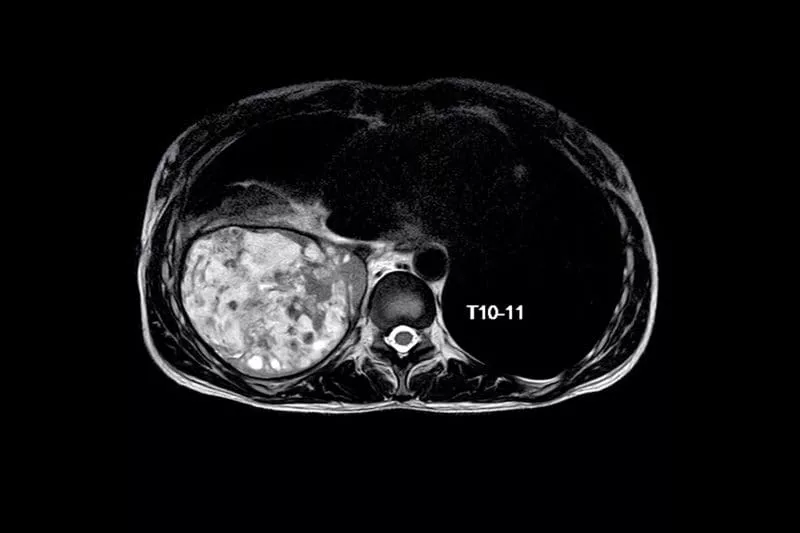

Axial MRI scan of the thoracic spine at the T10–T11 level, showing the vertebra, spinal canal, and surrounding soft tissue structures.